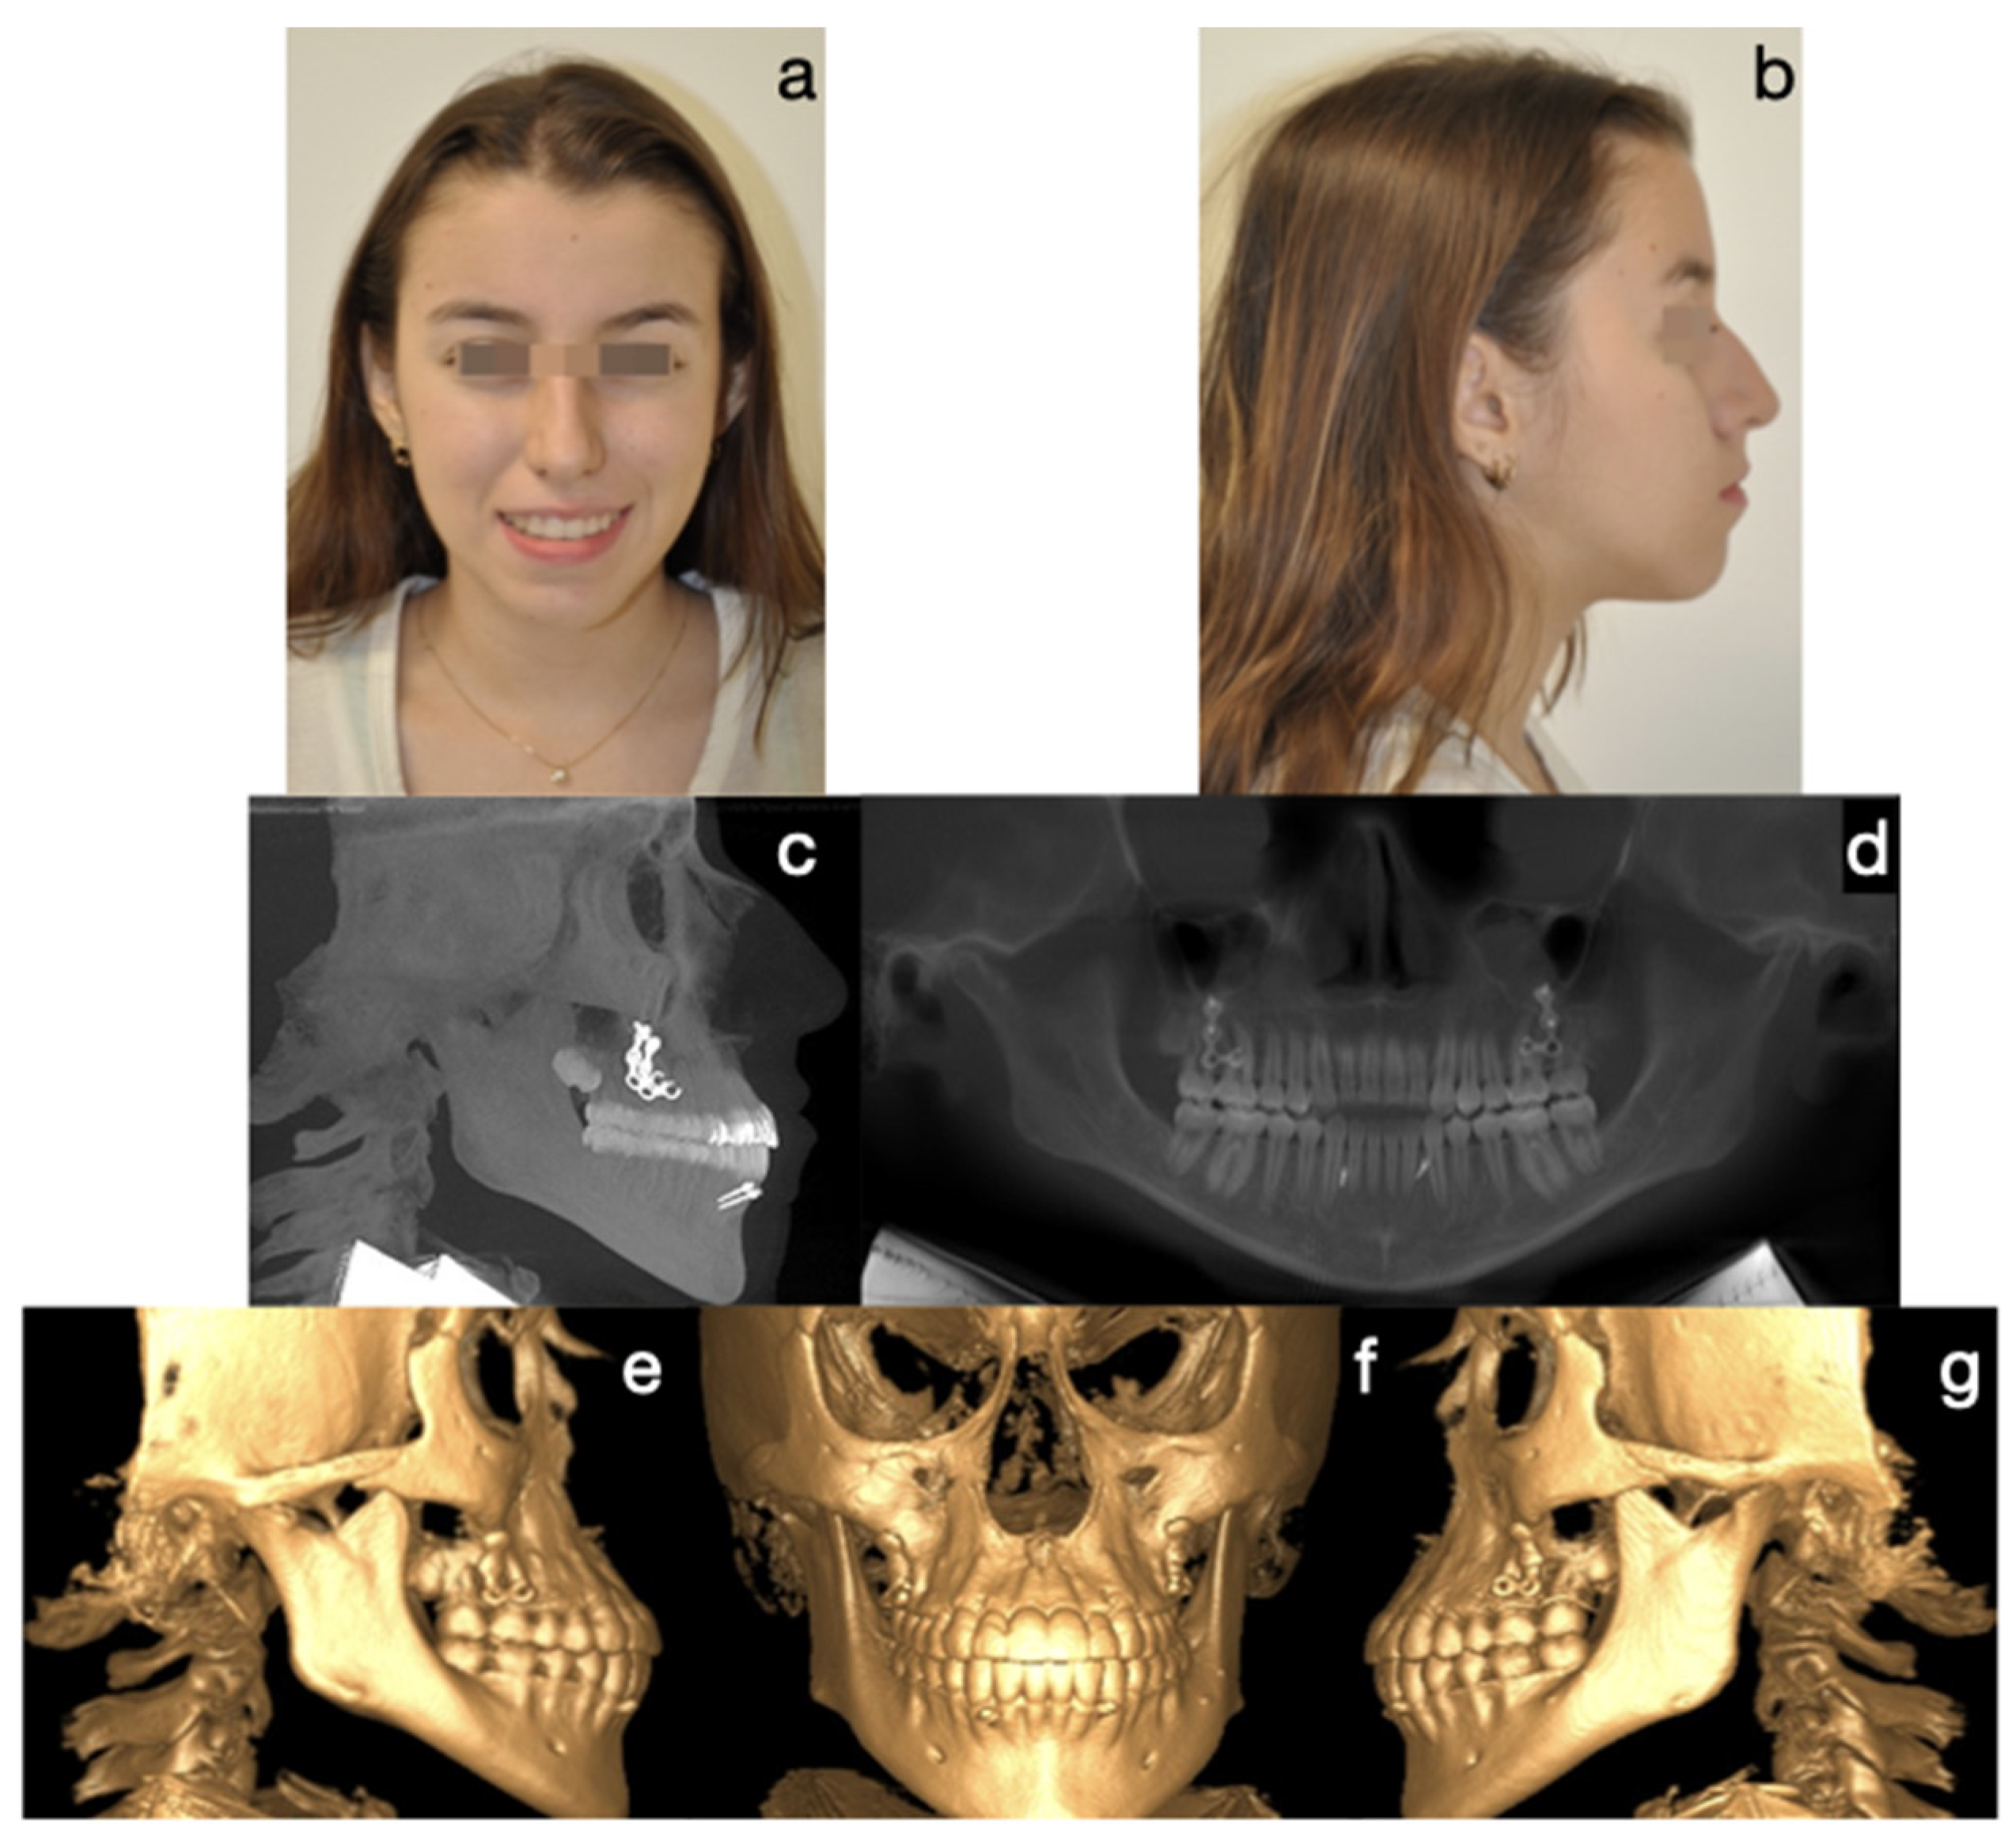

Figure 10. Final photos. Correction of the skeletal discrepancy, positive overjet, and adequate incisor emergence profile. Zygomatic plates and symphyseal screws were kept for the retention stage. (a) Frontal extraoral photograph, (b) lateral extraoral photograph, (c) lateral skull radiograph, (d) panoramic radiograph, (e) lateral CBCT, (f) frontal CBCT, (g) left lateral CBCT.

Protocol C followed in frequency (cases 2, 8, and 9), a single-surgical approach, involved bilateral condylectomy followed by orthodontics and/or orthopedics to correct sagittal discrepancies, avoiding a second surgery. One of the patients who followed this protocol is the one presented in Figure 7, Figure 8, Figure 9 and Figure 10, which show a 12-year-old female patient (Case 9, Table 1) with a severe mandibular prognathism that was accentuated after menarche. Anatomically, as evidenced by radiographic images, the condyles are elongated with posterior divergence but have normal anatomy. In addition, she has a lingual offset of the lower incisors. The result of the nuclear medicine test was 1.45 for the right condyle and 1.38 for the left condyle, confirming the active state of the CH. The surgical intervention consisted of a 5 mm high bilateral condylectomy. Histopathologic examination reported a soft condyle thickness of 0.6 mm for both condyles, with positive findings for CHB. In this case, in which the sequelae in the three planes of space were not severe and, additionally, there was growth potential, it was decided to correct the sagittal relationship of the jaws with skeletally anchored orthopedics and then with corrective orthodontics to achieve an ideal occlusion. In the active phase, the treatment lasted 24 months, and, in the follow-up phase, it lasted 48 months with adequate stability.